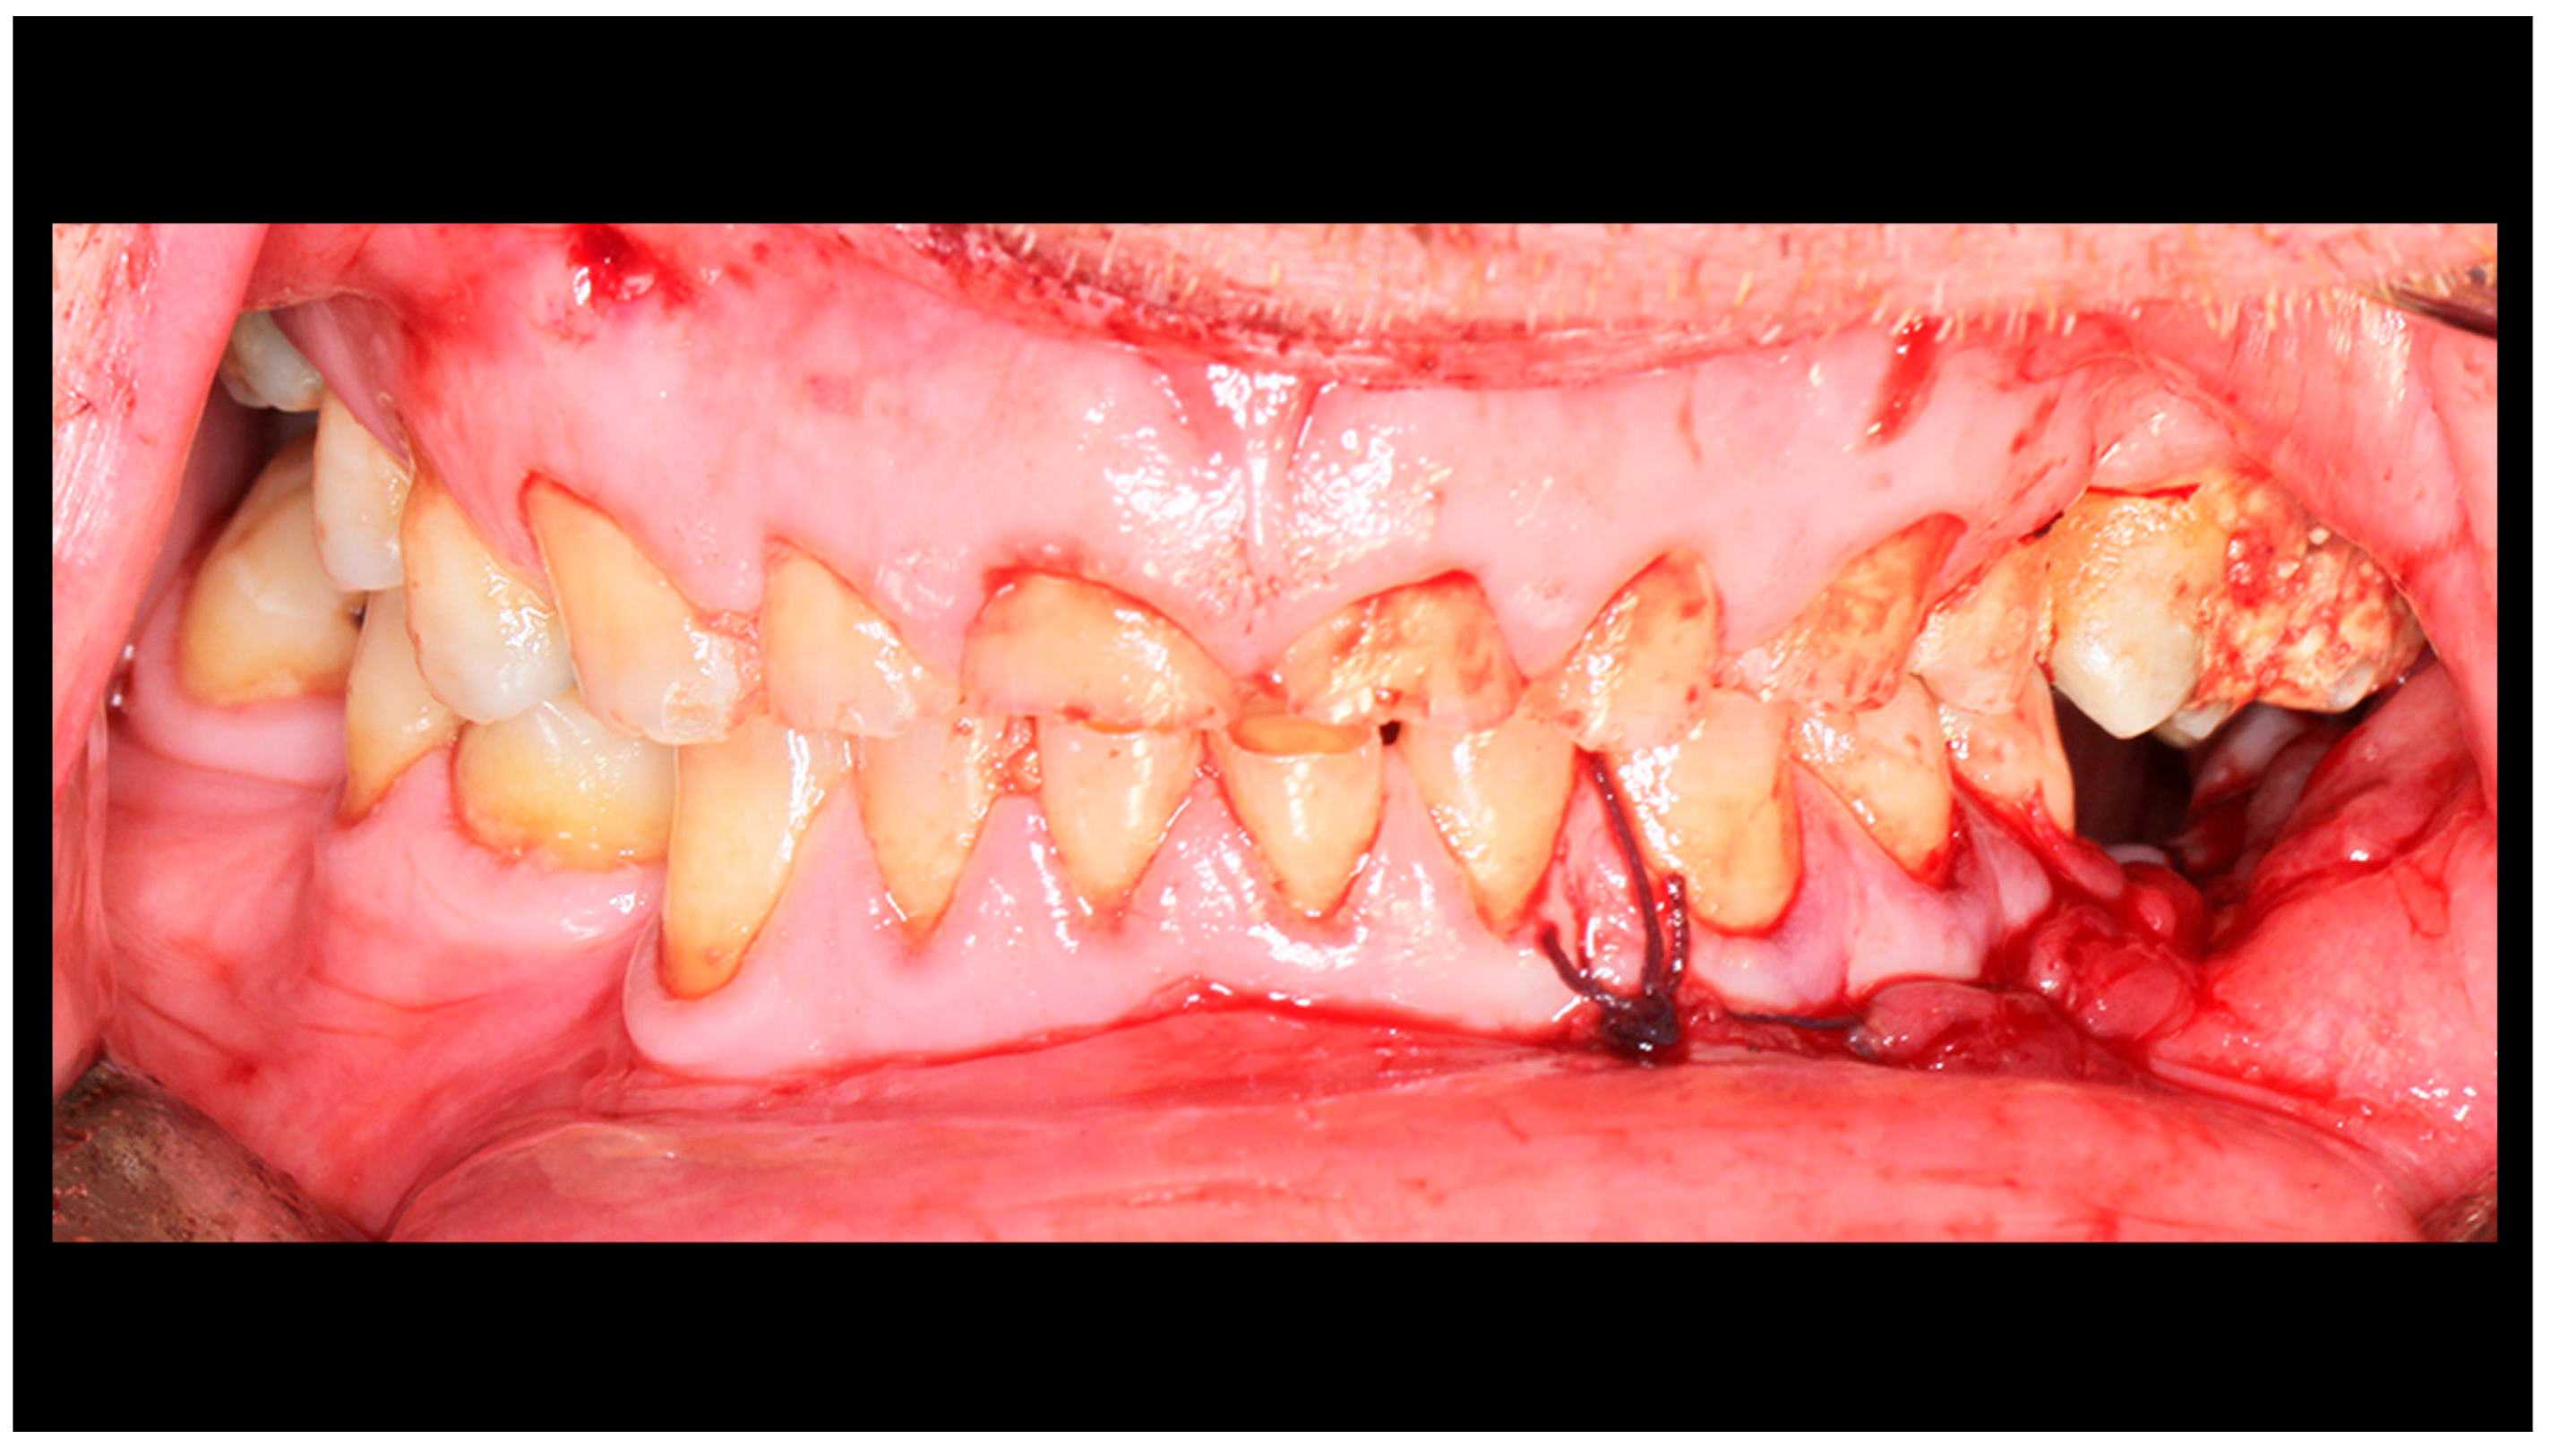

Figure 2.

Post-traumatic malocclusion. The mandible is divided into three pathological parts. The proximal fragments are displaced upward, while the distal fragment (the middle one) is displaced downward. This results in a completely open bite with dental contact only on the last teeth in the dental arch (red arrow). Please also note the break in the occlusal line resulting from an open fracture of the mandible on the left side (yellow arrow).